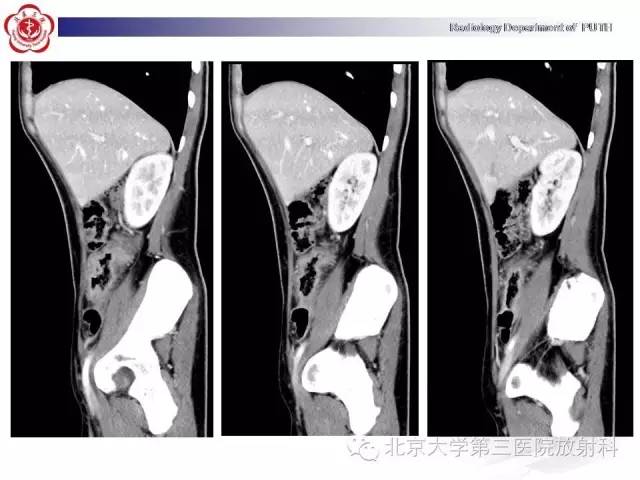

【病例】肠道白塞氏病1例X线CT